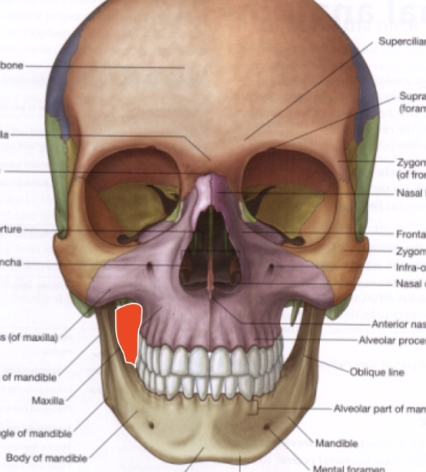

Apófisis maxilar

Cara externa articula con maxilar.

(aqui es cara externa)

Tuberosidad maxilar

pared anterior de la hendidura pterigomaxilopalatina

(Todo lo que se encuentra posterior a la apófisis cigomática)

Articula con la tuberosidad del maxilar anteriormente